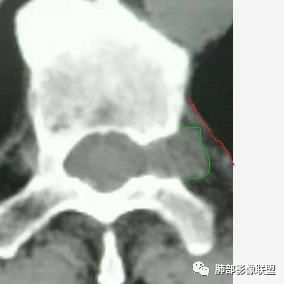

椎间孔很有价值吧

如果椎间孔增大,应该考虑神经源性的

大雄:所以还是得看潘老师说的椎间孔

问题是大病灶,而且椎间孔没累及

5.相邻椎间孔未见扩大,也未见块影延入椎管,易起自于神经根的鞘瘤似乎找不到相关支持点。